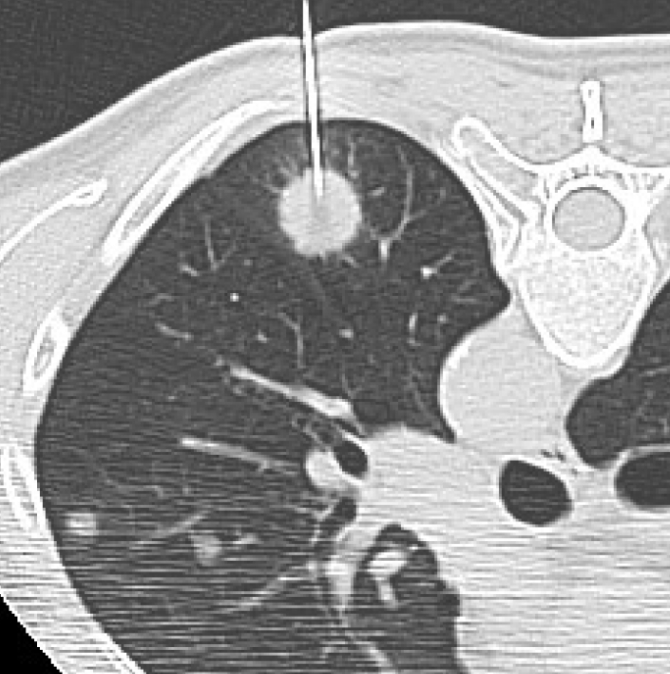

흉부 엑스레이 폐암

폐암은 초기에 특별한 증상이 거의 없어서 조기 발견이 어렵습니다. 흉부 엑스레이는 폐암을 찾아내는 첫 번째 단계로 사용돼요. 작은 혹이나 결절이 보이면 추가로 저선량 CT(방사선량이 적은 컴퓨터 단층촬영)를 진행하게 되죠.

하지만 엑스레이만으로 모든 폐암을 잡아내긴 어려워요. 종양이 아주 작거나 혈관 뒤쪽에 숨어 있으면 안 보일 수도 있습니다. 그래서 흡연력이 있거나 가족력이 있는 분들은 1년에 한 번 정도 저선량 CT를 병행하는 게 좋아요. 저희 아버지도 금연 후 매년 CT를 찍고 계신데, “한 번 찍으면 마음이 편하다” 하시더라고요. 그 말이 참 와닿았어요. 예방이 곧 안심이니까요.

Q3. 흉부 엑스레이에서 결절이 보인다고 하는데, 꼭 암인가요?

A. 대부분의 결절은 암이 아닙니다. 예전 감염의 흔적이나 석회화된 조직이 남은 경우가 훨씬 많아요. 하지만 결절의 크기나 모양, 가장자리 윤곽이 불규칙하다면 악성 가능성도 있으므로 정기적인 추적검사를 권합니다. 요즘은 저선량 CT로 더 정확하게 관찰할 수 있습니다.